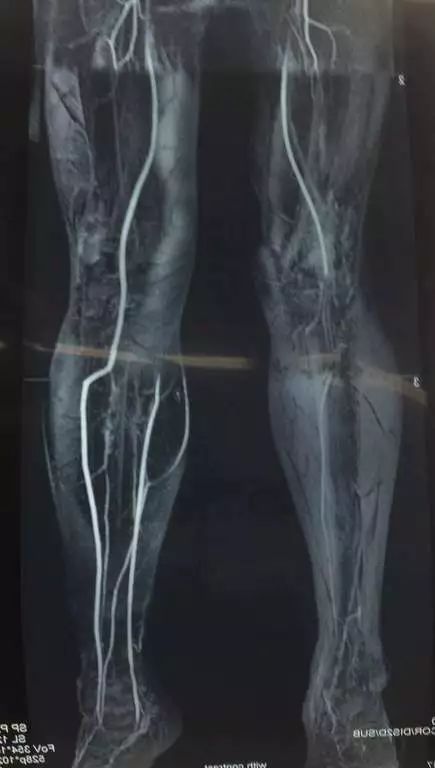

(网友提供)最后的病例是伤后40天由外地转来。开放骨折外固定架固定,骨坏死外露,用连珠和双氧水冲洗。入院时还存在足下垂,腓神经损伤、胫后动脉损伤。

• 入院6个月腓总神经恢复,胫前动脉再通